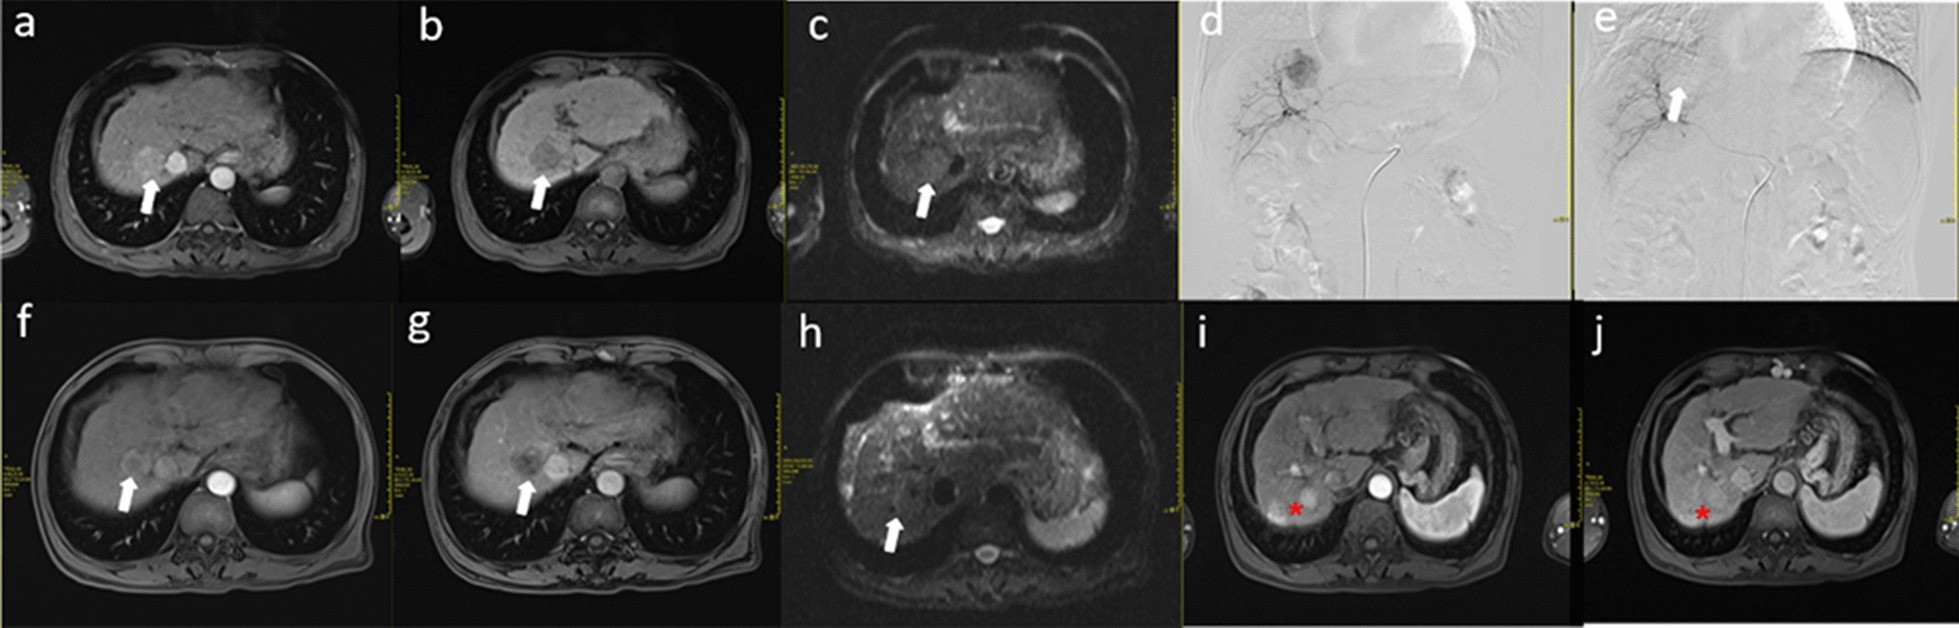

Fig. 3

MRI and digital subtraction angiography (DSA) images of a patient receiving early RFA (5 days) after TACE treatment. a–c The lesion (white arrow) showed a rapid increase in signal intensity during the hepatic arterial phase and the portal venous phase; the entire lesion (white arrow) showed rapid washout of the contrast material and became hypointense compared with the surrounding liver parenchyma. Diffusion-weighted imaging (DWI) showed the dispersion constant. d, e DSA images before and after the initial TACE treatment; the tumour staining disappeared (white arrow). f–h One month after combined treatment, the entire lesion (white arrow) showed necrotic foci in the centre, and DWI showed no dispersion constant. i–j After 48 months, there were two lesions in the liver, indicating long-term recurrence (red star sign)